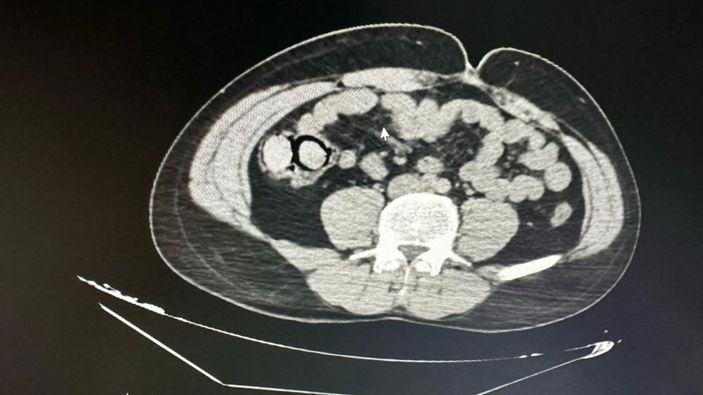

Gerçekleştirilen iç beden muayenesinde, 10 parça halinde toplam 113 gram metamfetamin ele geçirildi. Gözaltına alınan şahıslar, emniyetteki işlemlerinin ardından çıkarıldıkları mahkemece “uyuşturucu madde ticareti yapmak” suçlamasıyla tutuklanarak Elazığ Kapalı Ceza İnfaz Kurumu’na gönderildi.